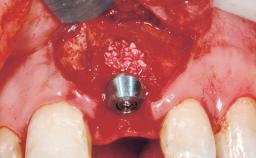

Immediate Flapless Placement of an Implant in a Maxillary Left Central Incisor Site

| Placement Protocol | Immediate implant placement |

| Tooth Site | Maxillary incisor or canine |

| Socket Morphology | Single-root socket |

| Socket Integrity | Damage to one or more bone walls |

| Bone Volume | Damage to one or more socket walls |